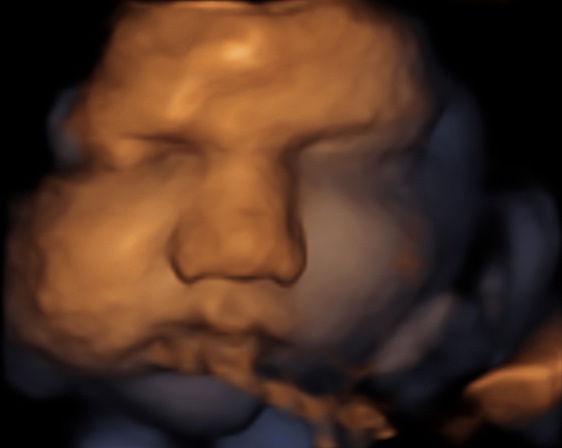

8 weken

12 weken

16 weken

21 weken

25 weken

30 weken

34 weken

37 weken

39 weken